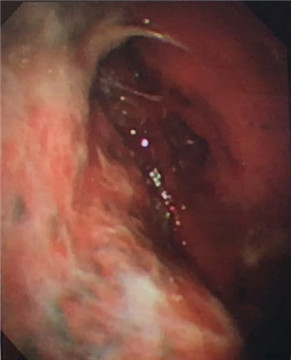

大量帶狀、網狀黏連帶

我院呼吸內科采用改良型“軟式胸腔鏡”,該新設備軟硬結合,前端可彎曲,能多方向觀察胸腔內改變,比老式“硬式胸腔鏡”的探查視野更大,診斷更準確。